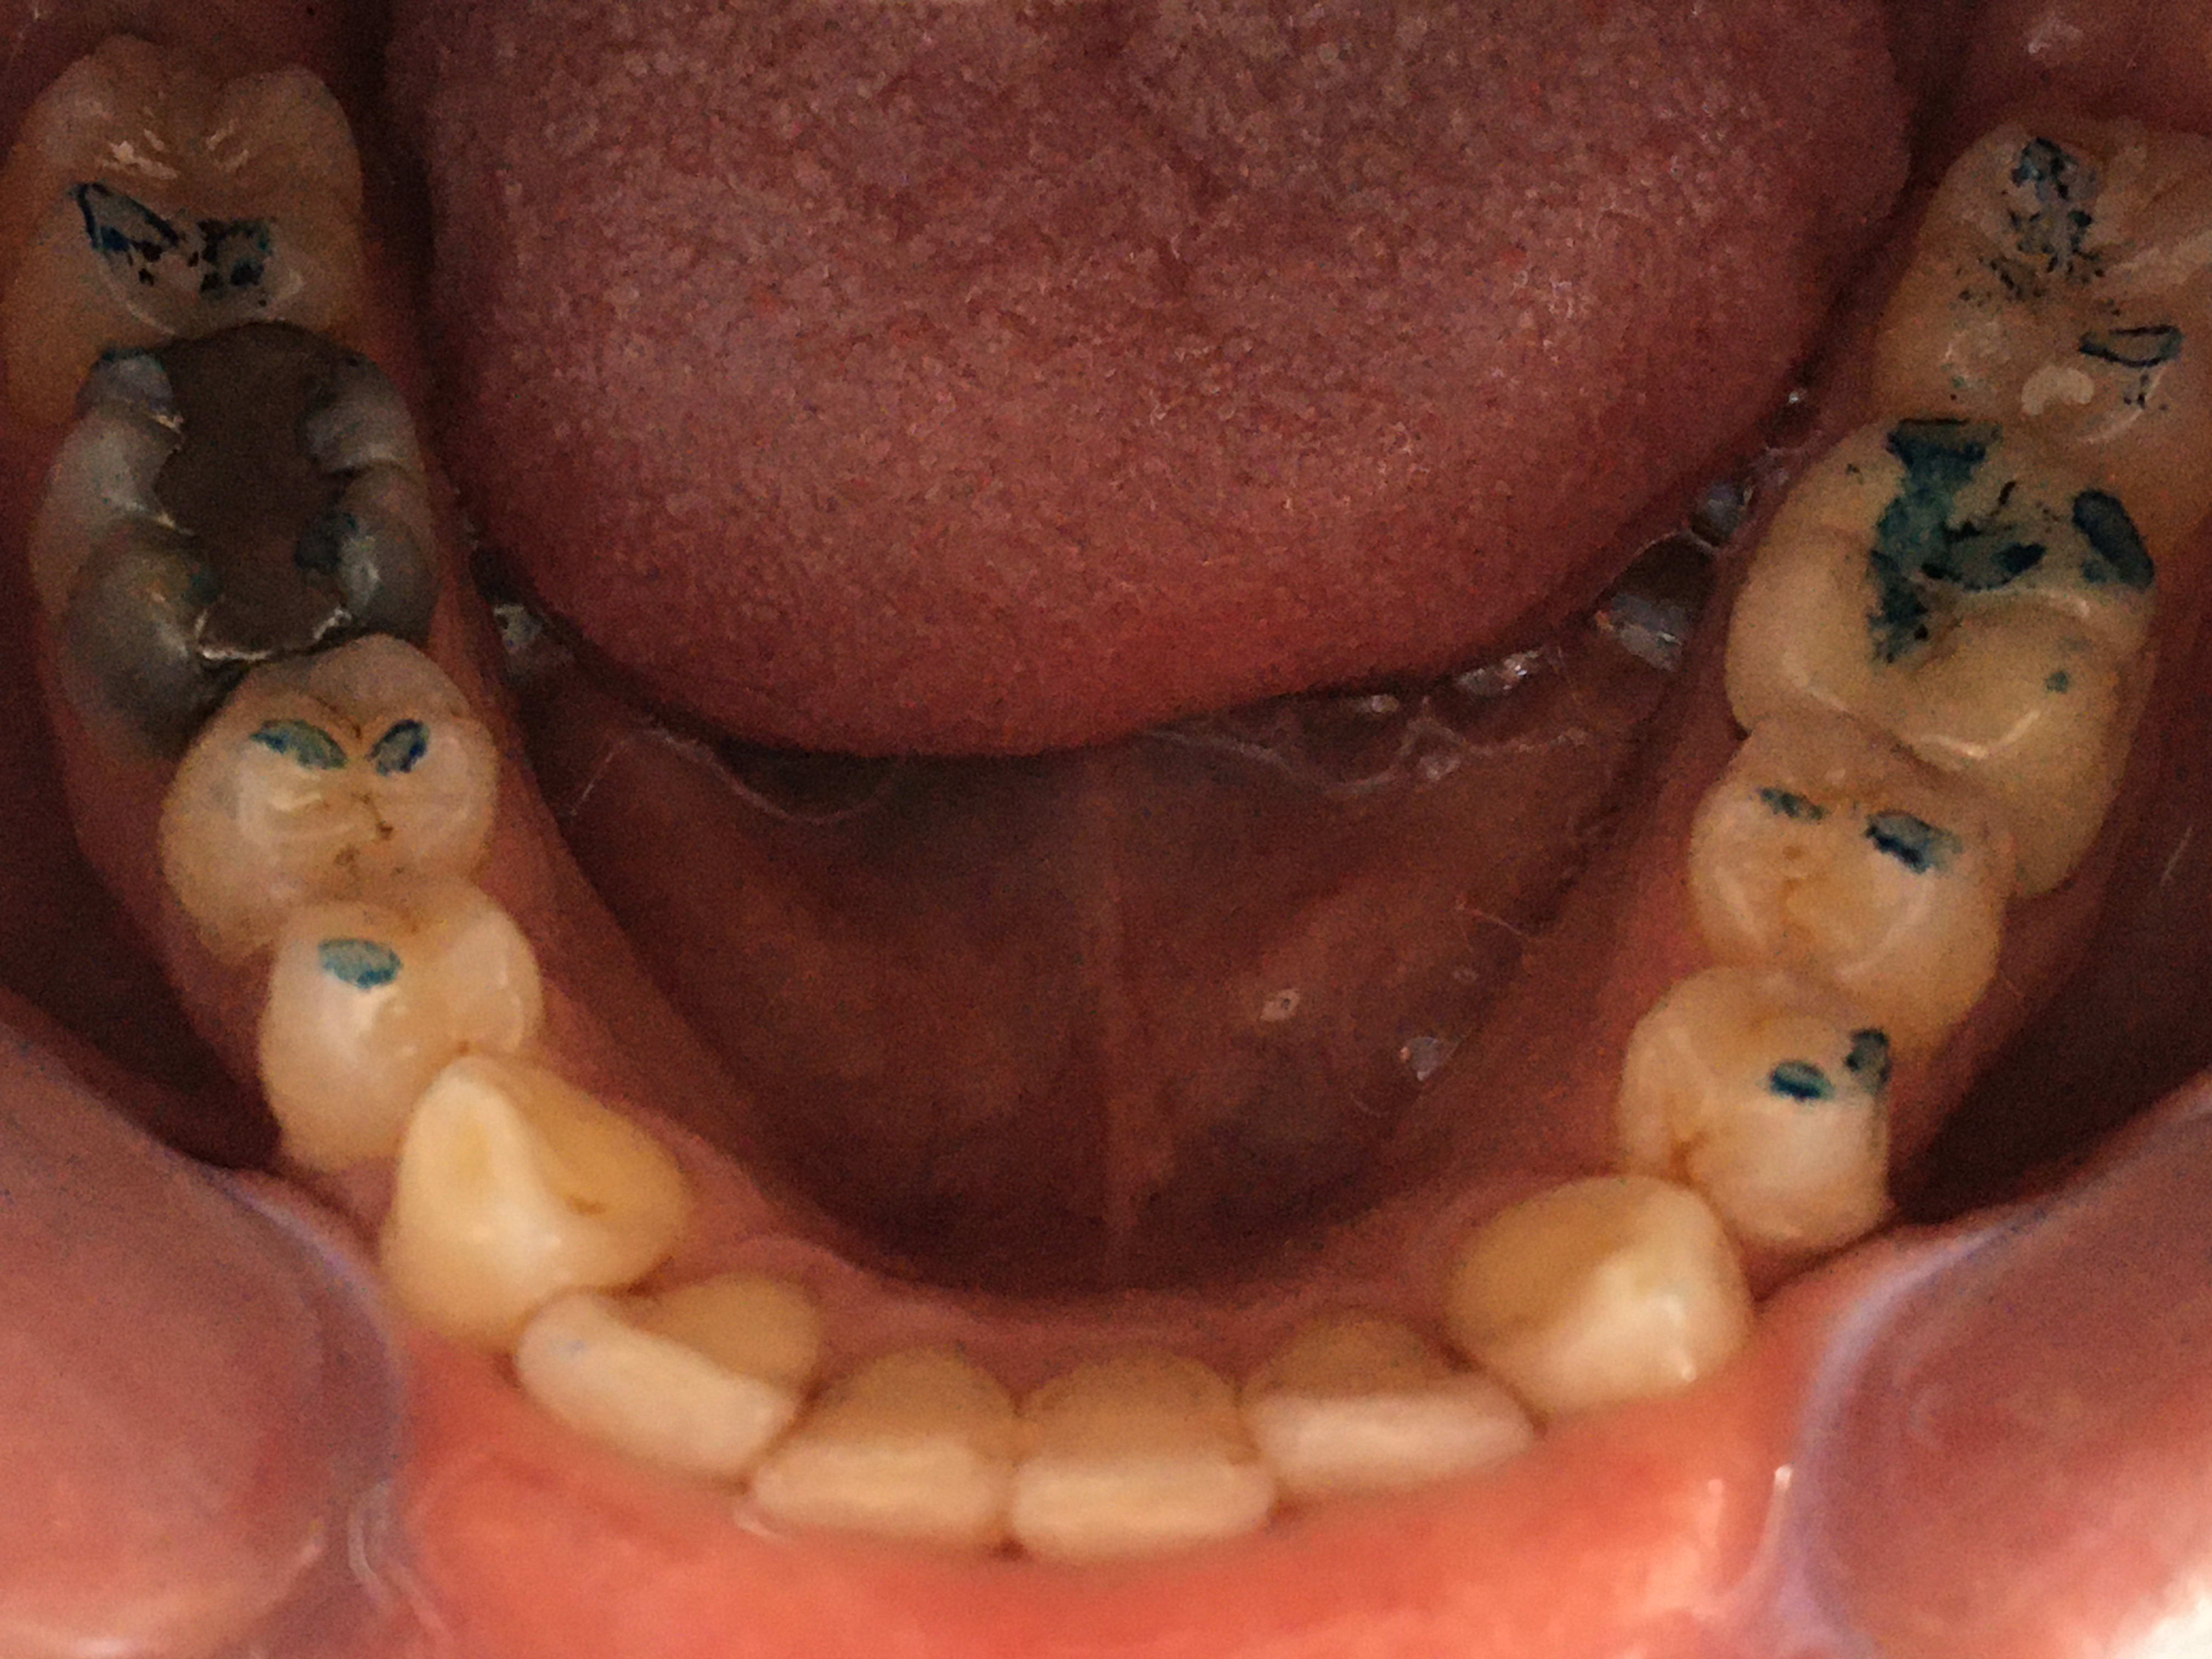

Photos vites faites Contacts en oim

On dirait bien une grosse surocclusion sur la coiffe 36

mais c est quoi ce bordel ??

mais Montmartre , pourquoi tu ne nous as pas montré cette photo avant ????

je ne comprends pas , tu as fais un gig et tu n avais pas vu ces points de fou avant ??

et tu me fais tout un vier sur la taille du papier , des faux positifs et tout le con de manon que oui que non , et que la vie est complexe ? alors que ç est gros comme un nez au milieu de la figure !

C'est fou, j'avais pas remarqué çà. En même il doit avoir plusieurs OIM différentes, çà doit être une qu'il ne m'avait pas encore montré :)

Bon je vais allé lui retoucher un peu çà, attendre que çà se tasse un peu, j'ai pas envie de lui couronner la 16 sans savoir où je met les pieds.

Le gars est allé il y a 12 ans chez son dentiste qui lui a fait une coiffe sur 36 en sur-occlusion. Il s’y adapte tant bien que mal, comme l’a dit sethef, sauf à des périodes de stress de sa vie où il a des crispations musculaires. Il retourne chez lui qui lui fait une gouttière de bruxisme. 36 étant en sur occlusion et 16 a un amalgame mis au pouce en sous occlusion, il y a eu égression de la 16 occasionnant une interférence en latéralité.